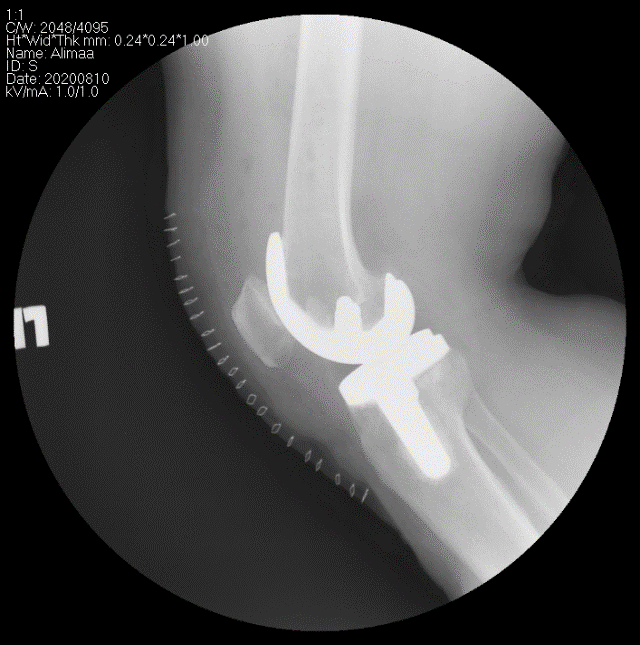

Өвдөгний үе бүтэн солих мэс засал (TKA) image4

Хөдөлгөөнт загвар

Хөдөлгөөнт загварын хиймэл үе нь дунд чөмөгний болон шаант ясны имплантын дундах полиэтилин жийргэвч нь эргэх хөдөлгөөн хийгддэг учир залуу болон хөдөлгөөний идэвхитэй хүмүүст илүү тохиромжтой байдаг.